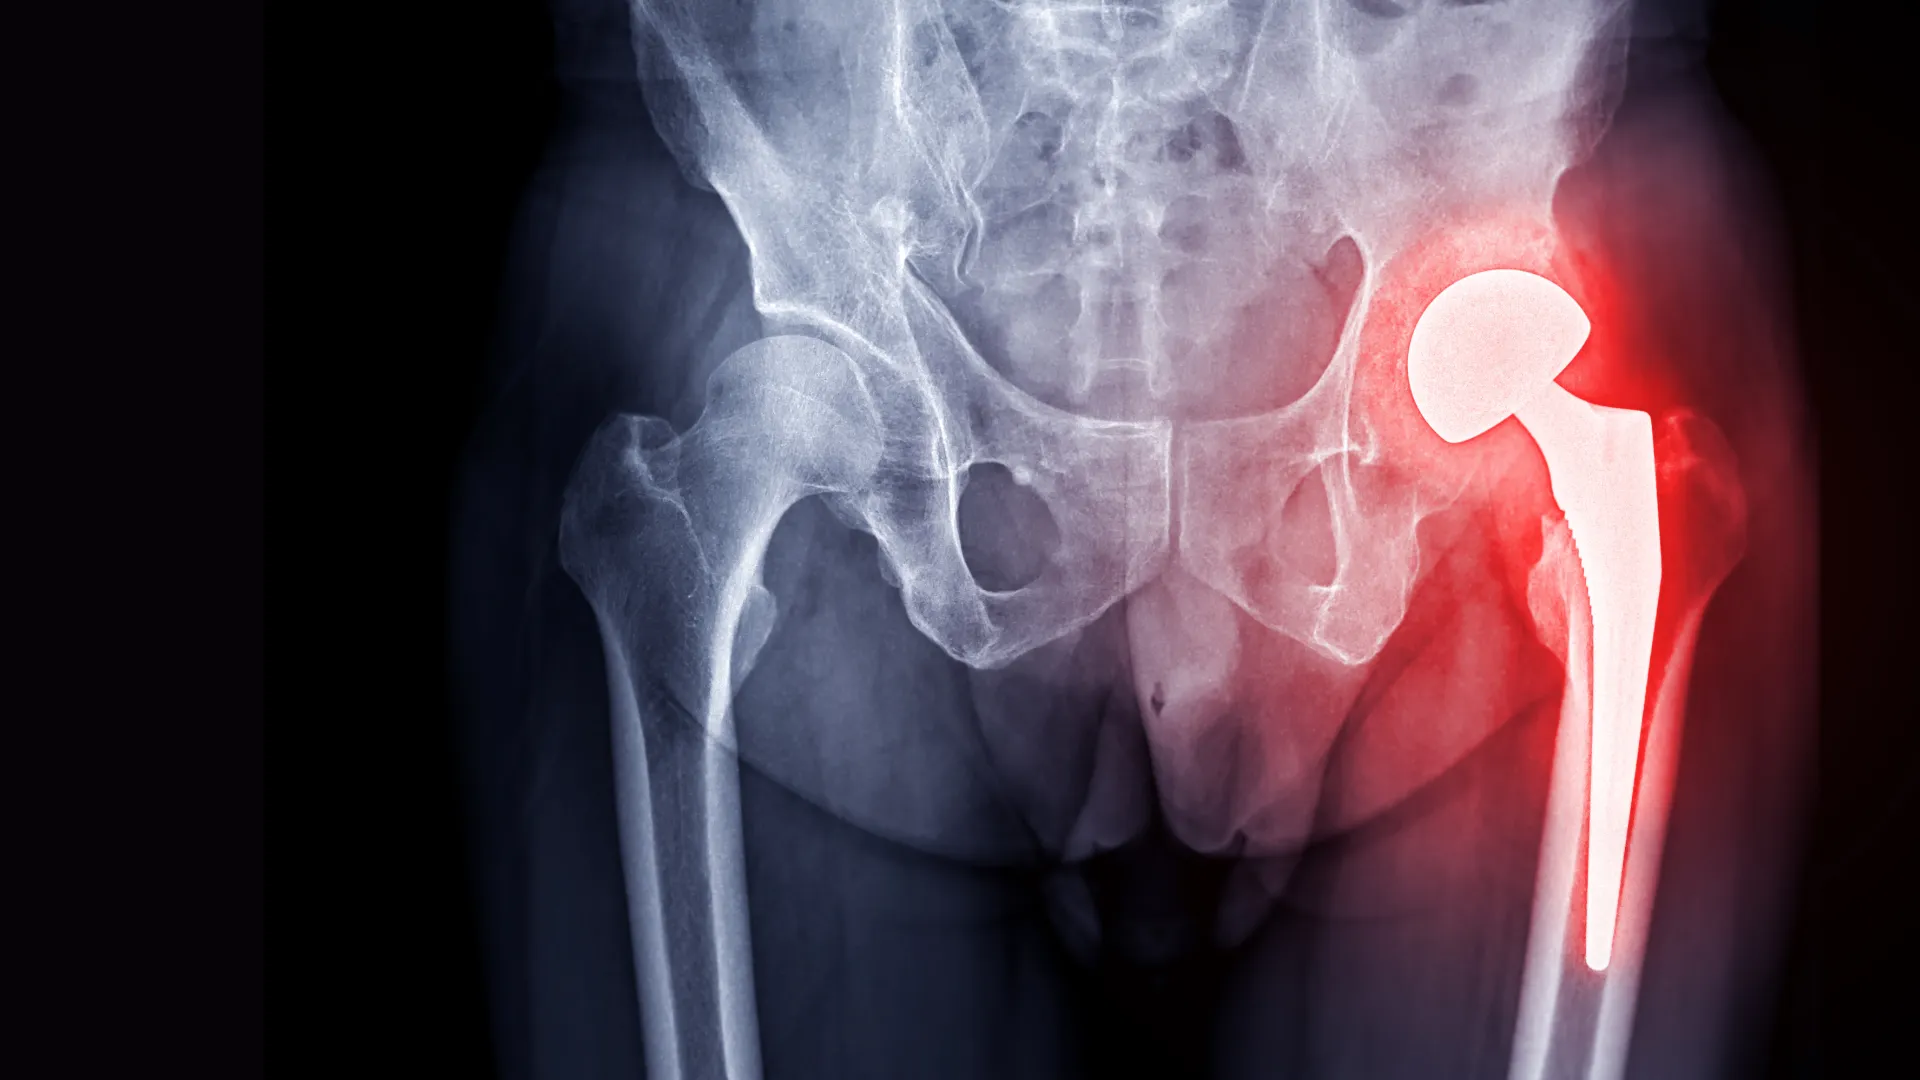

Ендопротезування — це сучасна операція, під час якої пошкоджений суглоб замінюється штучним імплантом. Протез повторює форму, функції та навантаження «рідного» суглоба — після відновлення ви знову рухаєтесь без болю.

Під час операції пошкоджений суглоб видаляють і замінюють ендопротезом — металевим, керамічним або комбінованим.

Хірург видаляє уражені хрящі та зруйновані частини суглоба. Це необхідно для підготовки до встановлення протеза.

Кістки обробляються, щоб забезпечити ідеальне прилягання штучного імплантату. Формується місце для фіксації компонентів протеза.

Після підготовки до кісток прикріплюються частини ендопротеза. Вони можуть фіксуватись цементним або безцементним способом.

Лікар перевіряє, наскільки рухливий і стабільний встановлений суглоб. Це дозволяє переконатися, що протез працює правильно.

Повна заміна всіх компонентів суглоба: голівки, чашки, суглобових поверхонь.

Цей тип втручання найчастіше застосовується при значному зношенні суглоба, де збереження окремих елементів неможливе.

Покази: важкий артроз, ревматоїдний артрит, остеонекроз, складні травми.